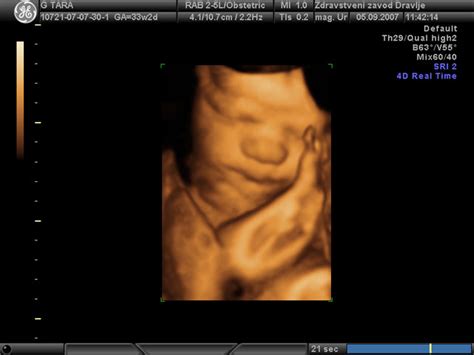

Ultrazvočna preiskava z uporabo 3D/4D tehnologije omogoča boljši pregled okostja, izključitev skeletnih nepravilnosti in anomalij nevralne cevi, ter pregled notranjih možganskih struktur in organov. Poleg medicinskega pomena, 3D/4D ultrazvok krepi čustveno navezanost staršev na plod.